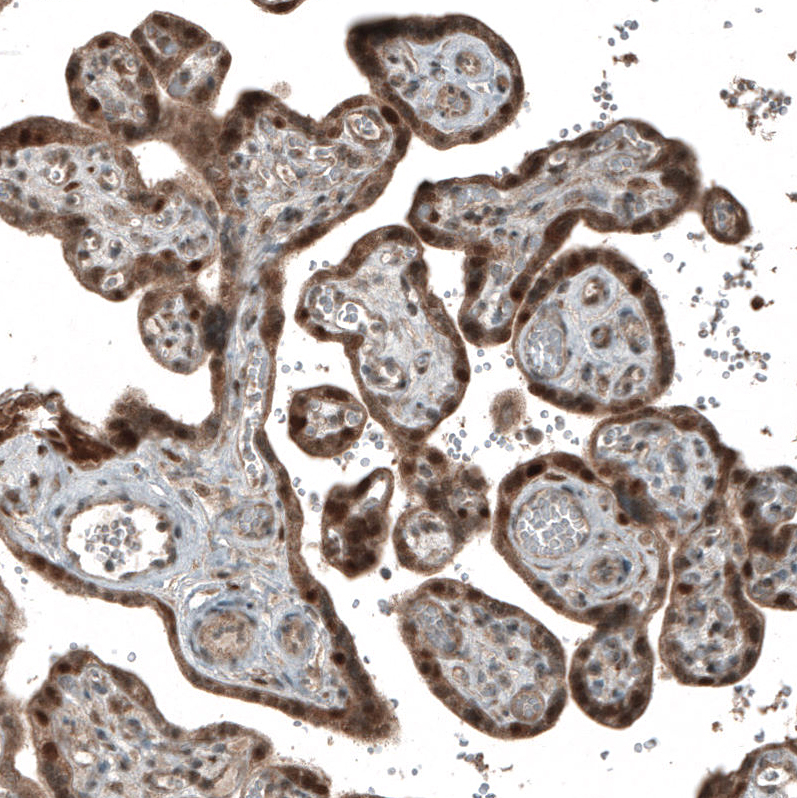

Immunohistochemistry analysis in human placenta and kidney tissues using AMAb91497 antibody. Corresponding CDK2 RNA-seq data are presented for the same tissues.